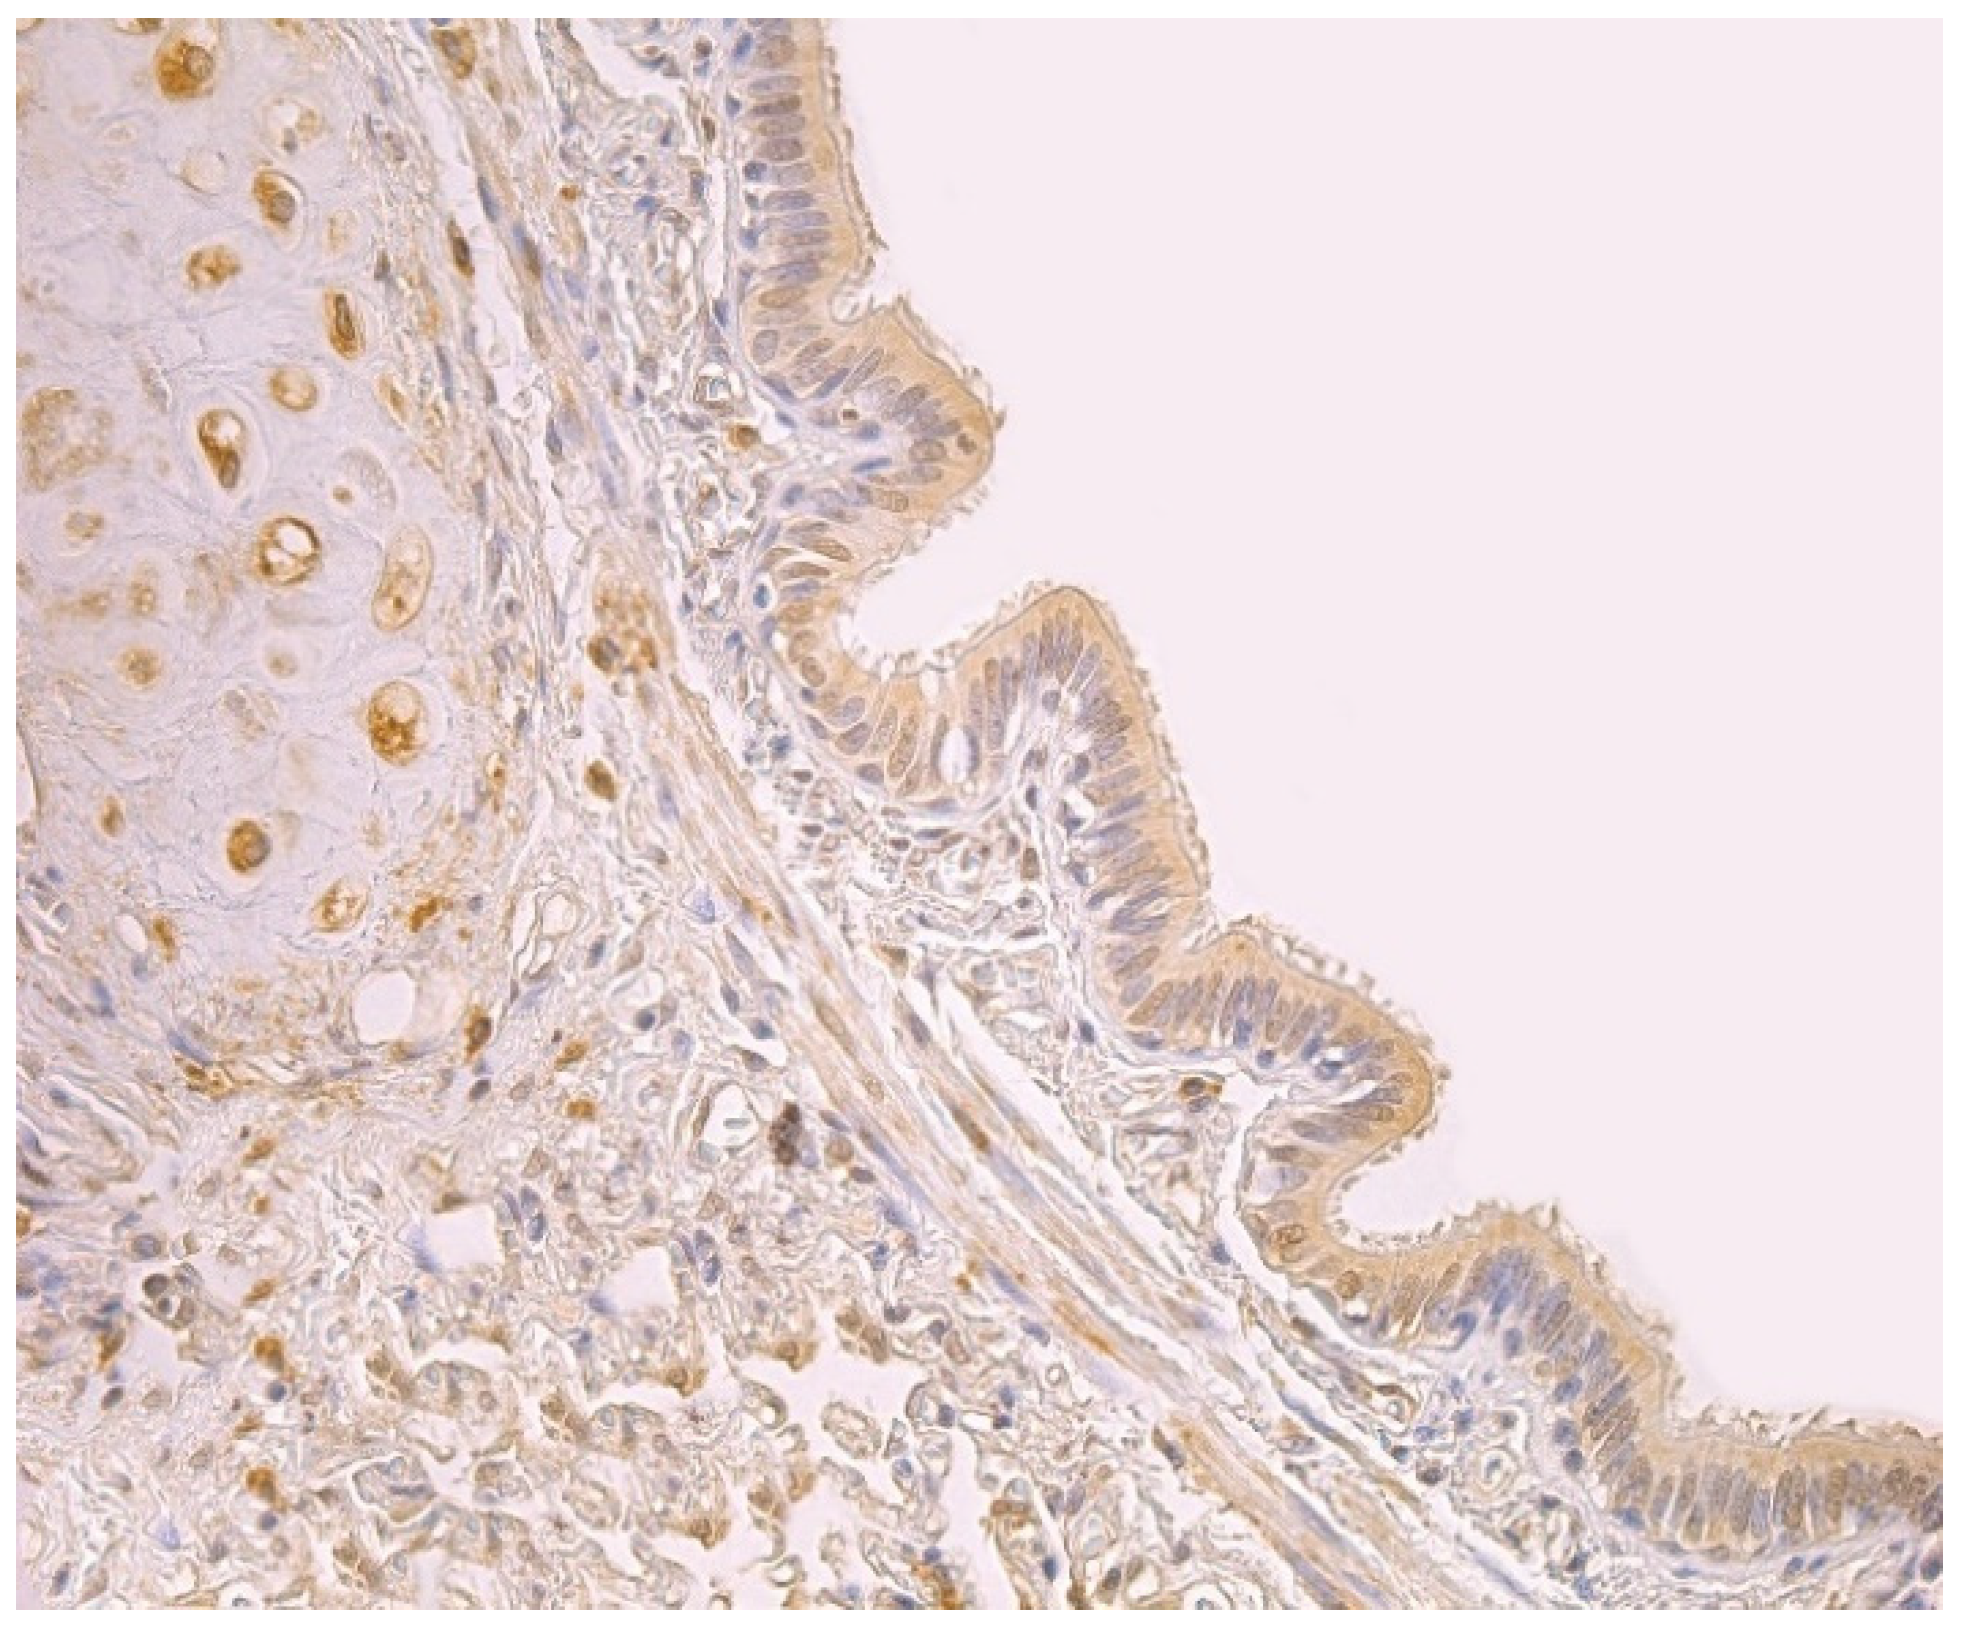

3.1. Tissue Review

3.2. Immunohistochemical (IMH) Data